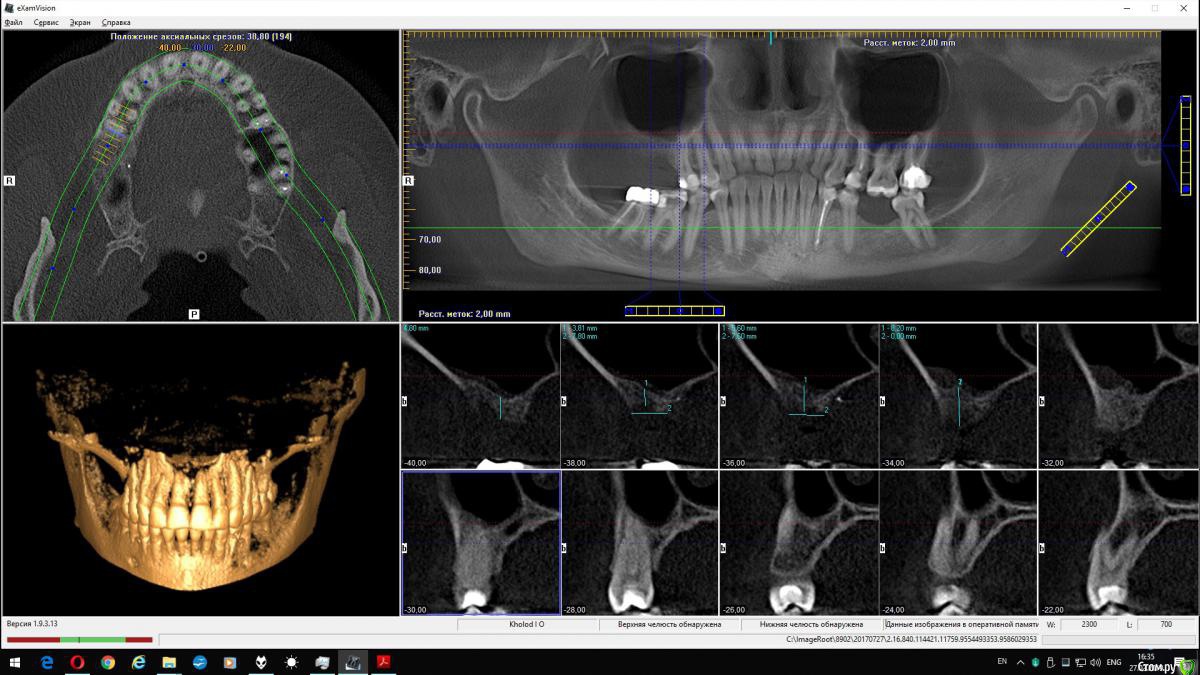

wladdX Опубликовано 27 февраля, 2019 Поделиться Опубликовано 27 февраля, 2019 (изменено) Скриншоты Сколько успел Изменено 27 февраля, 2019 пользователем wladdX Ссылка на комментарий

red_butler Опубликовано 27 февраля, 2019 Поделиться Опубликовано 27 февраля, 2019 соустье нужно посмотреть, но предварительно - не вижу препятствий для проведения открытого синуслифта Ссылка на комментарий

wladdX Опубликовано 27 февраля, 2019 Поделиться Опубликовано 27 февраля, 2019 Похоже, я загрузил скрины другого пациента (на диске записаны 2 исследования), исправляюсь. Ссылка на комментарий

kramer Опубликовано 27 февраля, 2019 Поделиться Опубликовано 27 февраля, 2019 Закрытый синус-лифт + 10 мм имплантат Ссылка на комментарий

red_butler Опубликовано 27 февраля, 2019 Поделиться Опубликовано 27 февраля, 2019 8 мм имплант и закрытый синус без графта Ссылка на комментарий

колесников Опубликовано 3 марта, 2019 Поделиться Опубликовано 3 марта, 2019 У вас речь идёт об одном импланты в области 16. Одиночный короткий Имплант не рекомендуется ни одним из производителей имплантов. Открытый синуслифтинг не показан из за особенностей строения пазухи в этой области,показан закрытый. Так же рекомендовал бы Астра тек,4.5х9. А также:дистализация 17го и имплантация в области 47.. либо удаление 17го,имплантация 17,16,47 Ссылка на комментарий